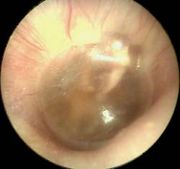

Otoscopic picture of Otitis media with effusion

Otoscopic findings: The tympanic membrane may be bulging, or retracted with a distorted cone of light. The ear drum may appear yellow, blue or simply clear white. Pneumatic otoscopy will reveal a ear drum which has a restricted mobility.